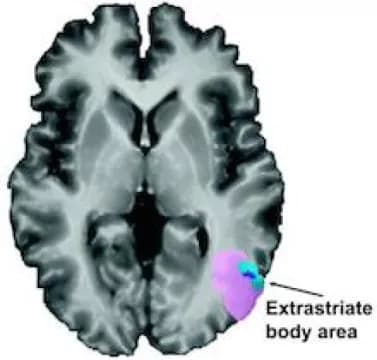

When study participants heard sentences that included phrases such as "shoulder responsibility," "foot the bill" or "twist my arm," they tended to engage a region of the brain called the left extrastriate body area or EBA.

"The EBA is part of the extrastriate visual cortex, and it was known to be involved in identifying body parts," says senior author Krish Sathian, MD, PhD, professor of neurology, rehabilitation medicine, and psychology at Emory University. "We found that the metaphor selectivity of the EBA matches its visual selectivity."

The Brain & Language paper includes analysis of "resting state connectivity," showing that the EBA appears to communicate with language processing areas of the brain, even while someone is not listening to a metaphor. Follow-up research could test whether magnetic stimulation of the EBA interferes with processing of body part metaphors.

In one reported case of damage to the brain including the EBA, the affected person was impaired in using body part words to refer to inanimate objects (the teeth of a comb or the arm of a chair). Separately, the EBA was recently shown to be involved in understanding the meaning of gestures.